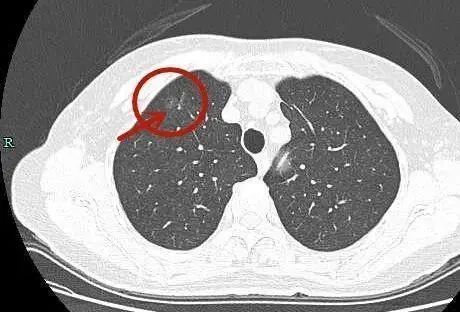

近日,吴齐在复查时,浙江省杭州市一医院放射科的曹捍波主任医师根据影像判断,他肺部6毫米的磨玻璃结节,最多是一个原位腺癌,“5年之内发生变化的概率在5%-8%,即使有变化,它的生长速度也非常慢,短期的复查根本看不出变化,一般要在两年半后才能看出变化。”

肺结节是影像学上的描述,指的是病灶的大小,而不是病灶的性质。在影像检查中,发现直径小于3厘米的病灶通常称为结节灶,当直径小于1厘米时常称为小结节。

根据肺结节的密度不同,可以分为纯磨玻璃结节、部分实性结节和纯实性结节。在这三类结节中,恶性病变分别占 18%、63%、7%。医生会结合病史、影像学结果综合判断。